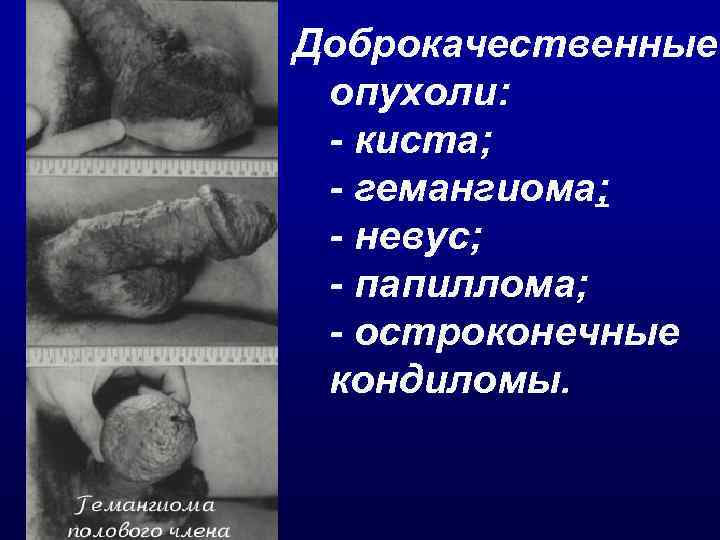

Доброкачественные опухоли: - киста; - гемангиома; - невус; - папиллома; - остроконечные кондиломы.

Доброкачественные опухоли: - киста; - гемангиома; - невус; - папиллома; - остроконечные кондиломы.